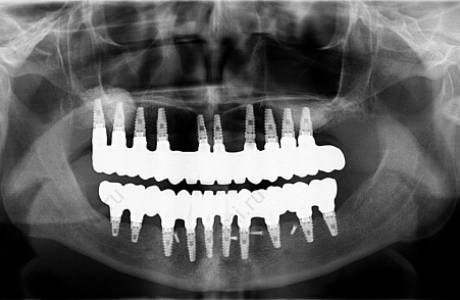

До лечения

Пациентка обратилась с жалобами на отсутствие зубов на верхней и нижней челюсти, снижение высоты нижнего отдела лица, невозможность носить съемные протезы. Принято решение об установке имплантов на обе челюсти с предварительными синус лифтингами и остеопластикой.

После лечения

По прошествии срока приживания имплантов были изготовлены металлокерамические коронки, основываясь на заданной форме и высоте временных коронок. Пациентка очень довольна результатом.

Пациентка обратилась с жалобами на отсутствие жевательных зубов на нижней челюсти, неудовлетворительный внешний вид ранее изготовленных конструкции.

При остмотре также выявлено занижение высоты нижнего отдела лица и полное отсутствие прикуса, при том, что у пациентки изначально был патологический прикус с глубоким резцовым перекрытием.

Принято решение провести тотальную реабилитацию прикуса, восстановление эстетики и высоты нижнего отдела лица.

На нижней челюсти установлены имланты. За время их приживления фронтальные зубы перелечены, восстановлены вкладками, на временных коронках зафиксирована нужная высота.

На все зубы были установлены коронки на основе диоксида циркония